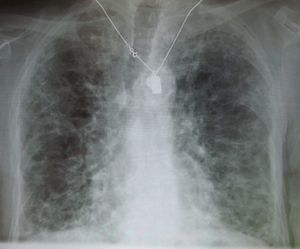

أشعة إكس على الصدر توضح حالة مصابة بالتيلف الرئوي. تاريخياً، كان يعتقد أن سبب التليف الرئوي هو الأميودارون.

• بإجراء الصورة الإعتيادية (الأشعة السينية) للصدر يتبعها إجراء صورة طبقية ذات المقطع الدقيق.